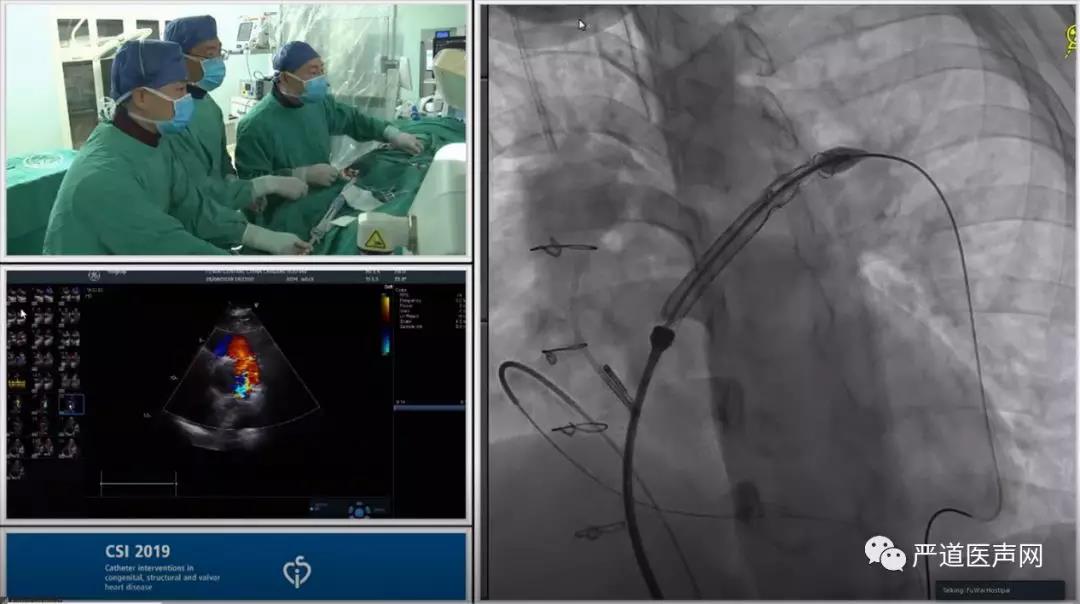

法洛四联症的心导管与造影检查

左侧股静脉,股动脉,然后于左侧股静脉,股动脉分别植入5f猪尾导管至肺